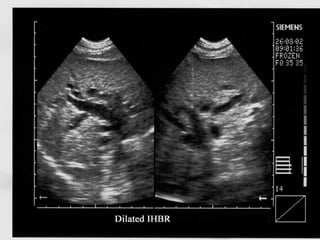

• Dilated IHBR seen as linear branching anechoic

structures parallel to the portal venous radicles

• IHBR more than 40 % of diameter of accompanying

portal vein or more than 2 mm in diameter is

considered dilated

• Normal CBD ranges from 5to 8 mm. Wider in

elderly and post cholecystectomy(upto 12) patients